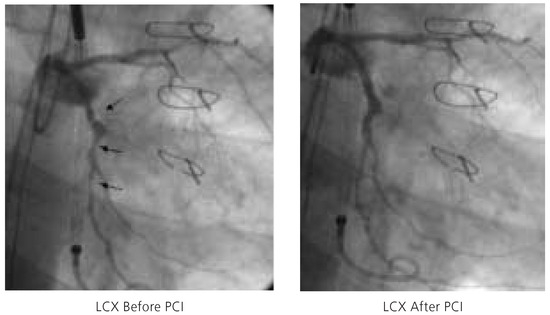

Impella Assisted High Risk Percutaneous Coronary Intervention

by Stephan Windecker and Bernhard Meier

Cardiovasc. Med. 2005, 8(5), 187; https://doi.org/10.4414/cvm.2005.01098 - 27 May 2005

Percutaneous left ventricular assist devices provide temporary circulatory support as bridge to recovery or heart transplantation in case of severe left ventricular failure and during percutaneous high-risk revascularisation procedures. We describe the first Swiss case of a high risk percutaneous coronary intervention assisted [...] Read more.

Percutaneous left ventricular assist devices provide temporary circulatory support as bridge to recovery or heart transplantation in case of severe left ventricular failure and during percutaneous high-risk revascularisation procedures. We describe the first Swiss case of a high risk percutaneous coronary intervention assisted by a new, percutaneously inserted left ventricular assist device: the Impella Recover® LP 2.5 pump. Full article

Show Figures

Figure 1